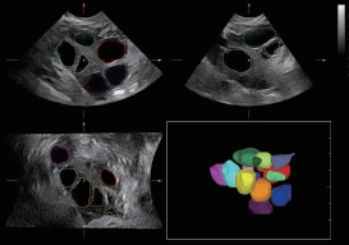

Sejak didirikan, Mindray terus mencari cara baru untuk meningkatkan keandalan diagnostik. Didukung Teknologi ZONE Sonography? terkini, platform ZST+ baru Resona 7 meningkatkan kualitas gambar ultrasound melalui pengambilan zona dan pemrosesan data saluran.

Selain kualitas gambar premium, Resona 7 juga meningkatkan kemampuan penelitian klinis dengan V Flow revolusioner untuk evaluasi hemodinamika vaskular, serta pengambilan penampang tercanggih dari rangkaian data 3D untuk diagnosis CNS pada janin. Kombinasi pengoperasian multisentuh berbasis gerakan yang paling intuitif dengan semua fitur klinis penting membuat Resona 7 menjadi gebrakan baru dalam inovasi ultrasound.